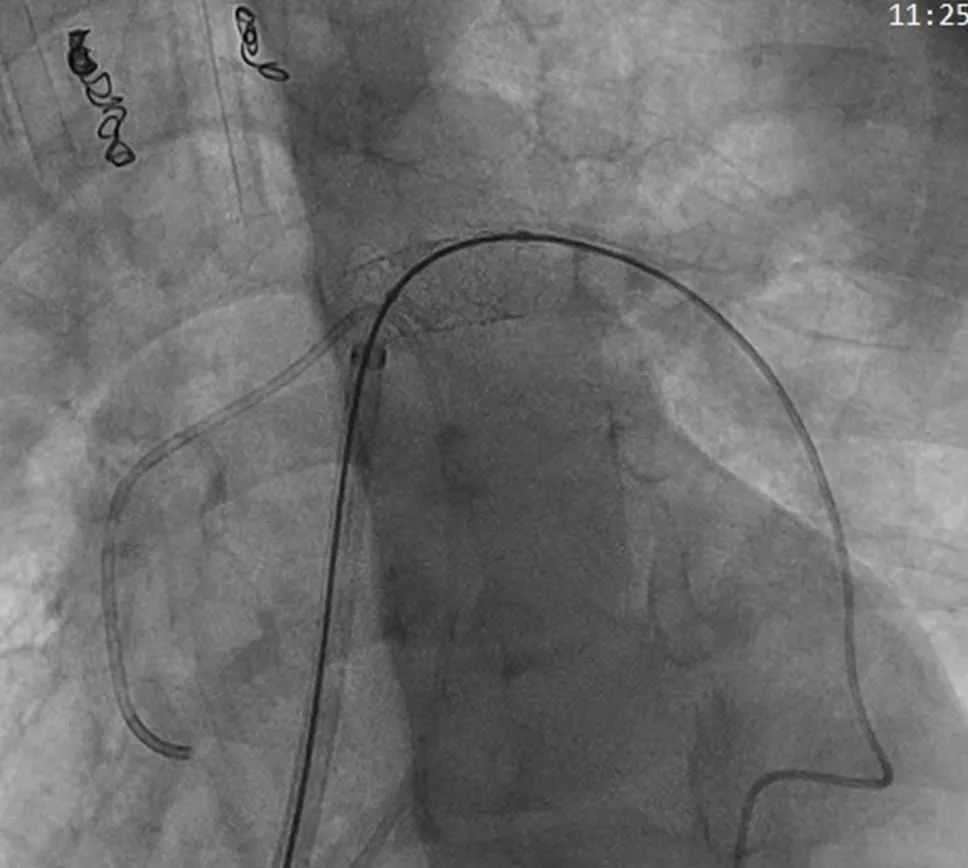

精确定位、释放后,通过造影发现,患儿肺动脉狭窄得到解决,右心室压力显著降低,手术获得成功。

支架扩张后